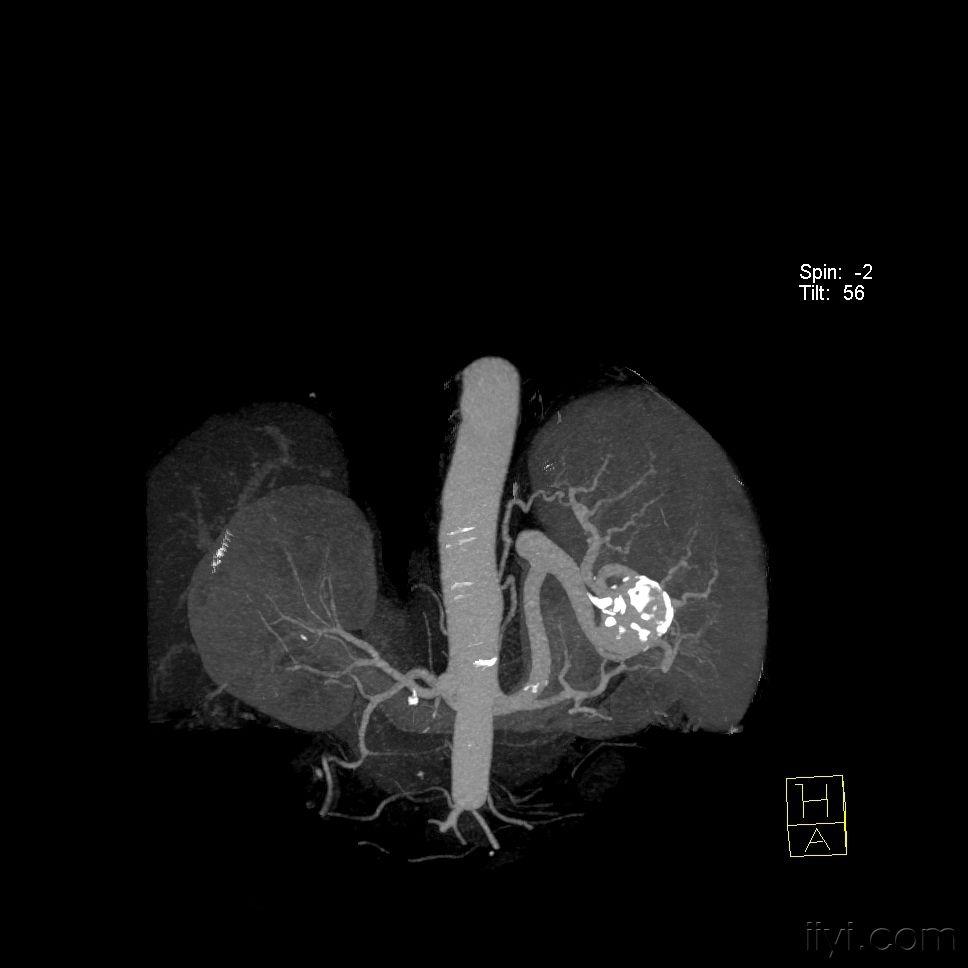

典型脾脏动脉瘤三维重建